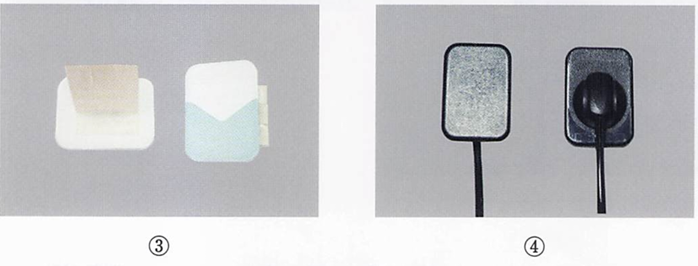

23歳の女性。上顎左側側切歯の着色を主訴として来院した。歯科医師から二等分法によるデジタルエックス線撮影を行う準備をするように指示された。 使用する器材の写真を別に示す。 この撮影に用いるのはどれか。2つ選べ。

a. ①

b. ②

c. ③

d. ④

解答を見る

a.d